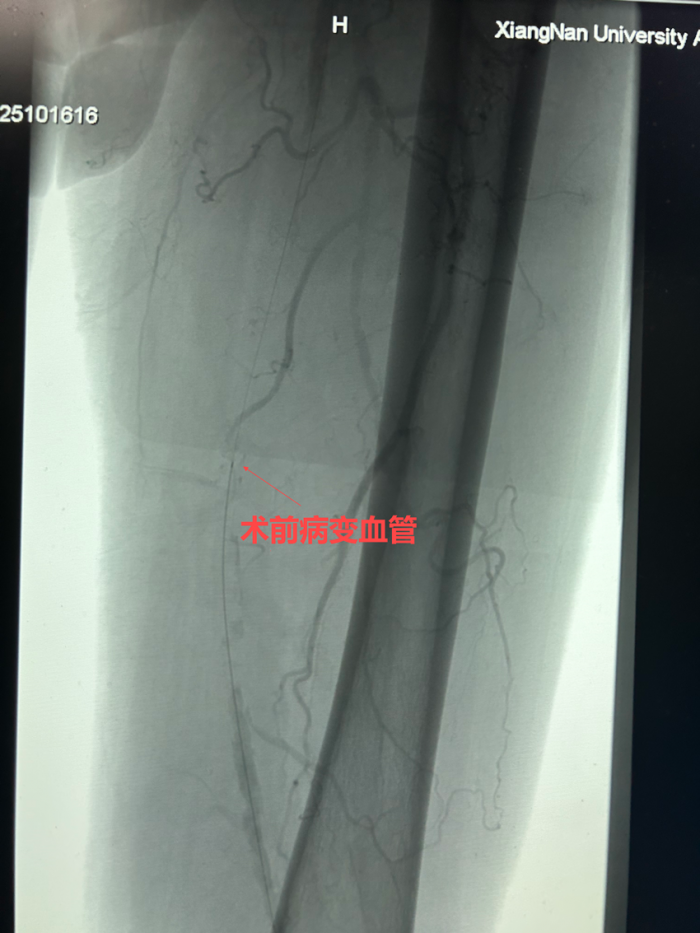

郴州市的王大叔今年66岁,已与糖尿病顽强抗争了 10 多年。近年来,双下肢间歇性跛行逐渐加重,每行走500米,下肢便疼痛难忍,生活质量严重受限。为寻求有效治疗,王大叔来到了湘南学院附属医院介入血管外科。入院后,彩超及 CTA 检查结果清晰地显示出双下肢动脉血管粥样硬化,多处狭窄且伴有多发斑块形成,病情不容乐观。

面对王大叔复杂的病情,周定中深知常规介入治疗方法难以应对。“患者合并症多,病变钙化严重,这给手术带来了极大挑战。” 周主任在查房时说道。经过团队的深入讨论,决定为患者实施斑块旋切辅助药物球囊扩张术。这一先进技术作为无异物植入(支架)的治疗方式,是下肢动脉血管微创介入治疗的新选择,有望为王大叔的下肢血管疏通带来新的希望。

手术当天,紧张的气氛弥漫在手术室。医生们通过股动脉穿刺,小心翼翼地将栓塞保护伞导入腘动脉,这一“保护伞”如同忠诚的卫士,准备兜住旋切过程中脱落的小斑块。在左股动脉中断,斑块旋切术正式开始。手术器械如同微型“刨子”,在直径仅几毫米的血管腔内辗转腾挪。医务人员凭借着精湛的技术,多次调整不同方向进行旋切刨吸。每一次切割都犹如在钢丝上行走,切得太薄无法达到治疗效果,切得太厚则可能损伤脆弱的血管。经过近两个小时的艰苦奋战,手术团队终于成功地将斑块切除并取出,随后药物球囊顺利扩张狭窄血管,抑制内膜增生,确保下肢动脉血流畅通。